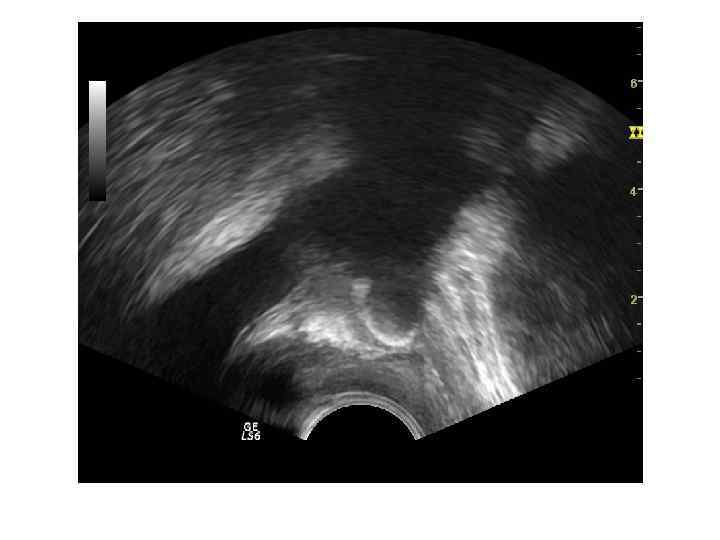

ДГПЖ Доброкачественная гиперплазия простаты – заболевание , характеризующееся гиперплазией железистых и стромальных элементов ткани предстательной железы. Основными источниками ДГПЖ являются переходные зоны и зона периуретральных желез.

Если происходит преимущественный рост переходных зон, образуются латеральные доли. Зональная анатомия предстательной железы при ДГПЖ. При ДГПЖ увеличивается объем переходной зоны (Tz), размеры центральной зоны (Cz) и периферической зоны (Pz) уменьшаются. Vm — семенной бугорок, А — фибромускулярная строма.

При росте периуретральных желез (ограниченных препростатическим сфинктером) образуется средняя доля.

При ДГПЖ меняются форма, размеры, структура и соотношение частей железы. Форма становится шаровидной или неправильной с выбуханием контура в просвет мочевого пузыря. При росте переходных зон происходит значительное увеличение размеров, но это не приводит к выраженной обструкции уретры. При росте периуретральных желез простата увеличена незначительно, но происходит сдавление уретры выбухающей средней долей. Структура гиперплазированных узлов неоднородная, часто с дегенеративными изменениями ( кисты, участки склероза, кальцификаты).